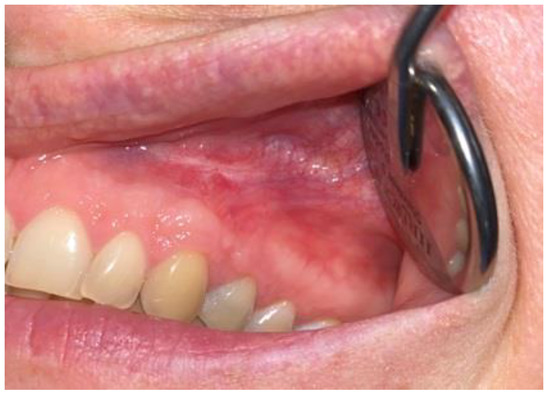

Figure 8. Intraoral photograph 3 days after surgery.

After-surgical wound care included 3 times per day rinsing with 0.1% CHX solution-Eludril 0.20% (Pierre-Fabre Oral Care); 3 times per day H2O2 hydrogen peroxide 3% (HascoLek, Wrocław, Poland) and appliance for sleep CHX gel solution on the wound. After local wound dehiscence, additional Solcoseryl dental adhesive paste (Meda Pharma, Solna, Sweden) was used to improve wound granulation (Figure 8). Wound hygiene was maintained for 14 days.